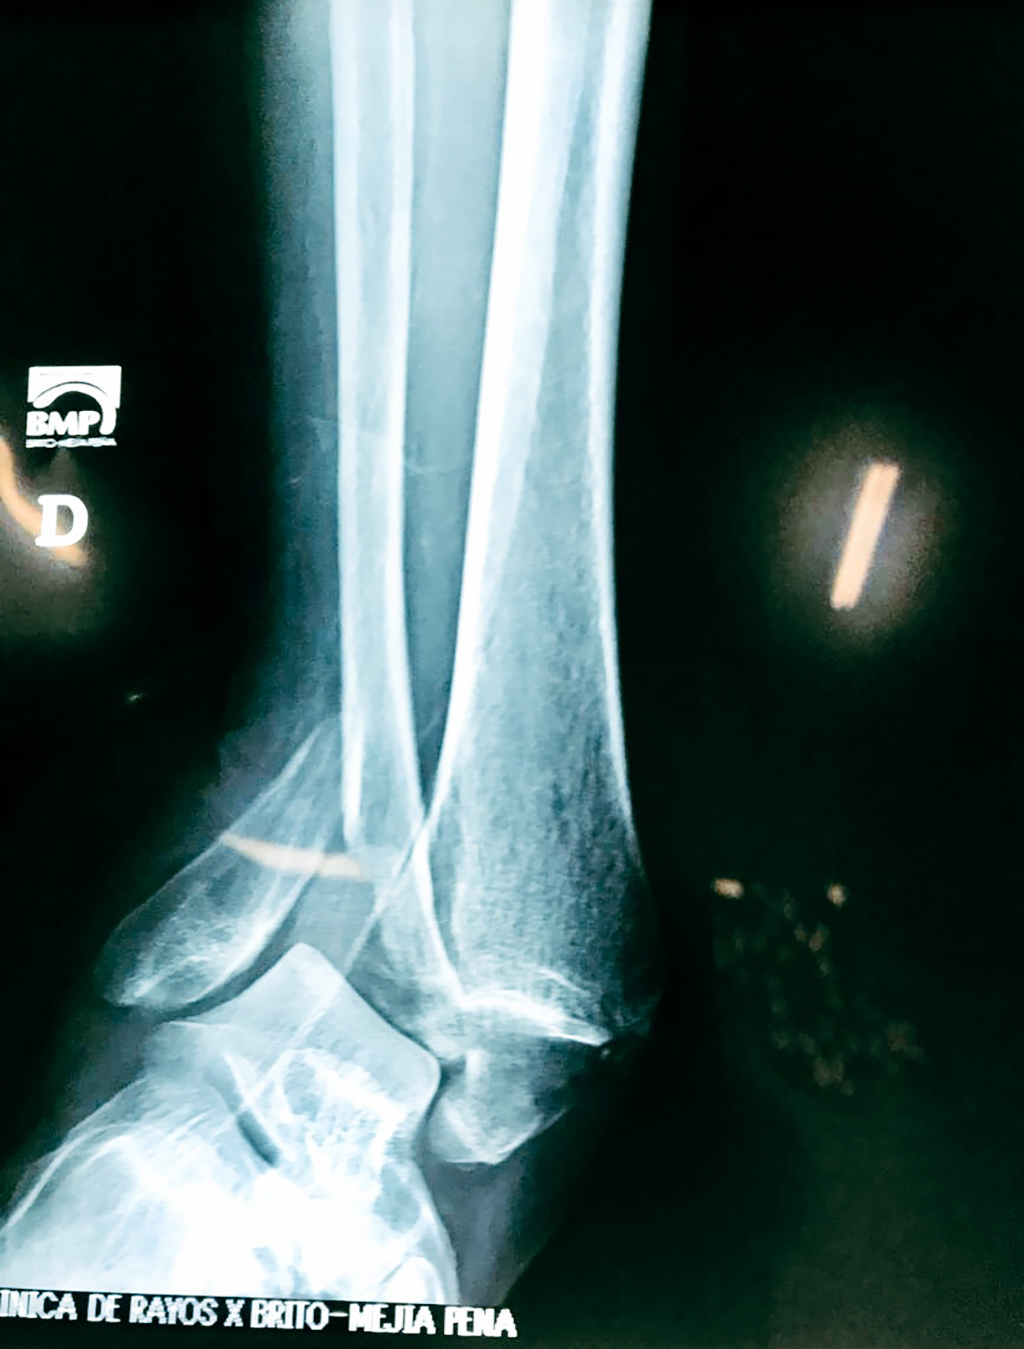

Una fractura de tobillo es la rotura de uno o más de los huesos del tobillo. Estas fracturas pueden ser:

- Los extremos de los huesos están desalineados entre sí (desplazados).

- La fractura se extiende hasta la articulación del tobillo (fractura intra-articular).